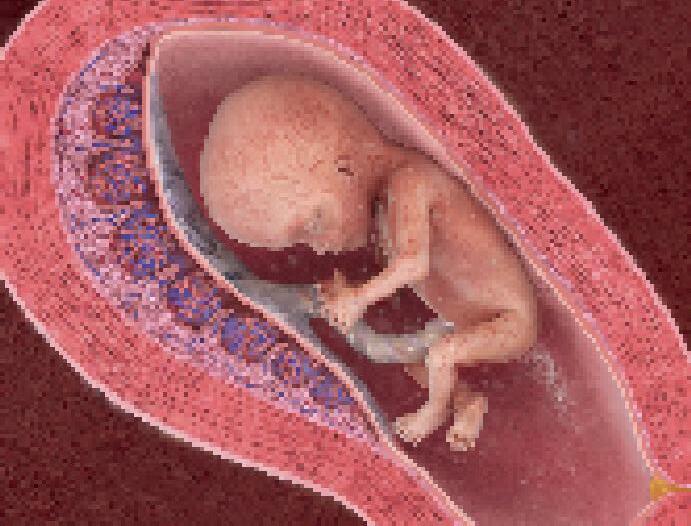

Vyživováno krví matky a chráněno jejím tělem se nenarozené dítě (plod) uvnitř dělohy rychle vyvíjí a každých čtyři až pět týdnů zdvojnásobuje svou hmotnost.

Třebaže si období života před narozením nedokážeme pamatovat, naše mozky a smyslové orgány už začaly pracovat. V pozdním stadiu těhotenství může nenarozené dítě vidět narůžovělou záři pronikající matčinou kůží, slyší její hlas, tlukot jejího srdce a hlasité šplouchání plodové vody. S použitím rukou a nohou zkoumá vodní svět kolem sebe a vnímá vlastní tělo. Nemůže dýchat, protože je ponořené v tekutině, ale zkouší sát a polykat. Po devět měsíců mu děloha poskytuje bezpečné, teplé a pohodlné prostředí, zatímco matčin krevní oběh zásobuje rostoucí tělo potřebným kyslíkem a živinami.

Připraveno se narodit

Ke konci těhotenství se plod otočí hlavou dolů, připraven se narodit. Jeho trávicí soustava je nyní schopná zpracovávat potravu, ale stále ještě získává živiny z matčiny krve prostřednictvím svazku cév – pupeční šňůry. V pokročilém těhotenství porůstá celé tělo plodu vrstva jemných chloupků, které před narozením obvykle zmizí.

Placenta Uvnitř placenty přecházejí kyslík a potrava z matčiny krve do krve dítěte.

Děloha Jak plod roste, stěna dělohy se roztahuje.

Oči se otevírají, když je plod 6 měsíců starý, ale dokážou jen rozlišovat světlo a tmu.

Rostoucí plod

Změna proporcí Protože mozek a nervová soustava se v rané fázi těhotenství rychle vyvíjejí, hlava roste rychleji než zbytek těla. Za devět týdnů zabírá polovinu délky plodu a vypadá obrovitá. Zbytek těla ji v dalších měsících dohání.

Všechny důležité orgány se objevují během prvních devíti týdnů života, kdy je vyvíjející se dítě ve fázi embrya. Od devíti týdnů dále se nazývá plod.

Po příštích sedm měsíců plod rychle roste. Složité tkáně a tělní soustavy se tvoří, sílí a začínají fungovat. Jsou položeny základy kostry, tvořené zprvu místo kostí pružnými chrupavčitými tkáněmi.

Pupeční šňůra Toto „záchranné lano“ přivádí kyslík a živiny z matky přes placentu do plodu.

Stáří 15 týdnů

Stáří 20 týdnů

Stáří 34 týdnů

Plod je velký jako křeček, s obrovitou hlavou a maličkým tělem. Rysy tváře jsou dobře patrné a plod zkouší dělat grimasy včetně úsměvu a mračení se. Polyká plodovou vodu a škytá tak silně, že to matka vnímá.

DÉLKA: 13 CM

Plod je právě za polovinou těhotenství, nyní dokáže pohybovat prsty, na nichž se vyvinuly papilární linie. Reaguje na zvuk a snadno se vyleká hlasitými zvuky. Matka začíná cítit, jak plod kope.

Plod je téměř plně vyvinutý. Tráví okolo 90 procent času spánkem a má sny. Trénuje dýchání vdechováním tekutiny asi 40krát za minutu. Dokáže cítit jídlo, které